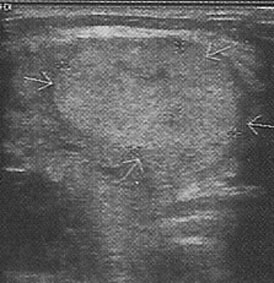

Ultrasonda nodülün içi tamamen sıvı ile dolu ise kistik nodül (şekil 1), tiroit kaynaklı doku ile dolu ise katı nodül (solit nodül) (şekil 2), hem doku hemde sıvı içeriyorsa karışık nodül (mikst nodül) (şekil 3) adını alır.

Şekil 1: Kistik nodül ![]() | Şekil 2: Katı nodül ![]() | Şekil 3: Karışık nodül ![]() |

Ultrasonda tiroit kanser riski bulguları: Çapı 2.5-3cm'den büyük olan katı (Şekil 4) ya da karışık nodüller, çapı 4cm'den büyük kistik nodüller, kenarları düzensiz (Şekil 5) ve/veya içinde küçük kireçlenme odakları bulunan nodüller (Şekil 6), içinde ve etrafında kan akımı artmış olan nodüller ve izlemler sırasında büyüyen nodüller riskli nodüllerdir. Bunlardan bir kaçının beraber bulunması riski arttırır.